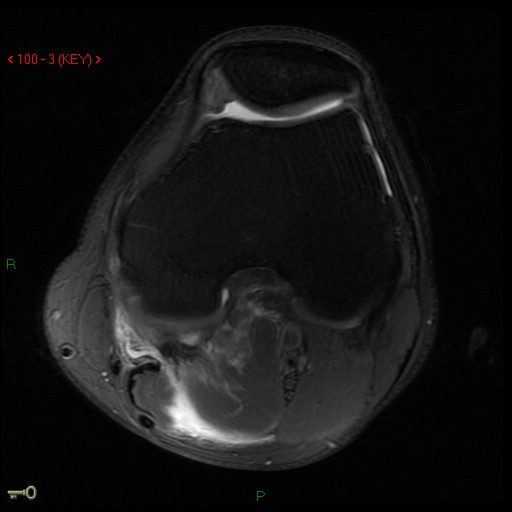

Figure 4 for case Medial head of gastrocnemius muscle ( RID2921 ) avulsion

Figure 4